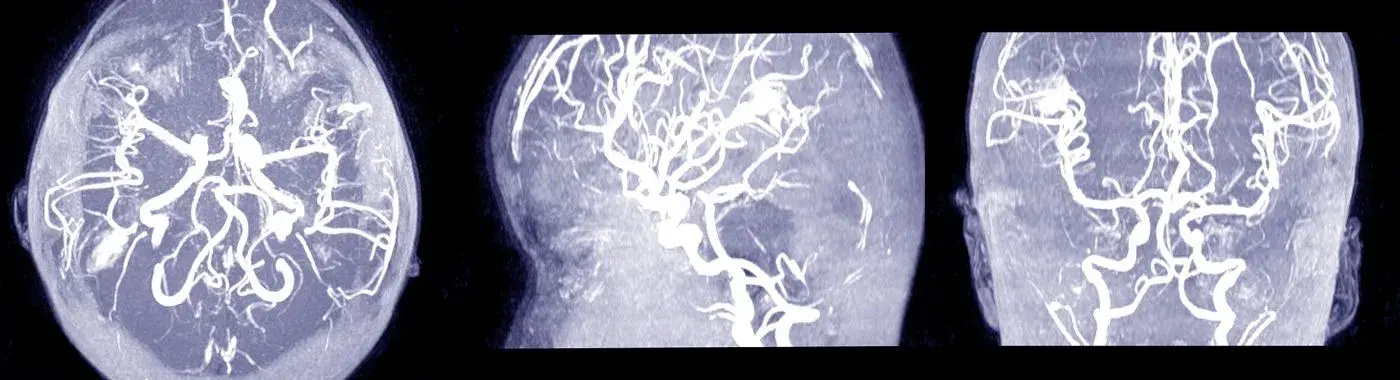

• Imaging Studies: Magnetic Resonance Imaging (MRI) and Computed Tomography (CT) scans are commonly used to visualize the brain and detect clots in the venous sinuses.

• Venography: This specialized imaging test involves injecting a contrast dye into the veins to visualize blood flow and identify blockages.